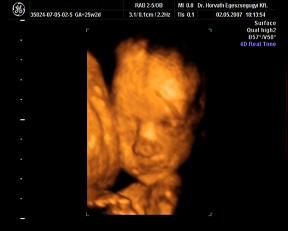

Néhány kép, nagyon kis drága volt, szépen mutatta magát:

egy 2D-s profil

És néhány 3D-s:

Kép Kép Kép Kép

Hát ilyenek vagyunk a 25. héten.:D